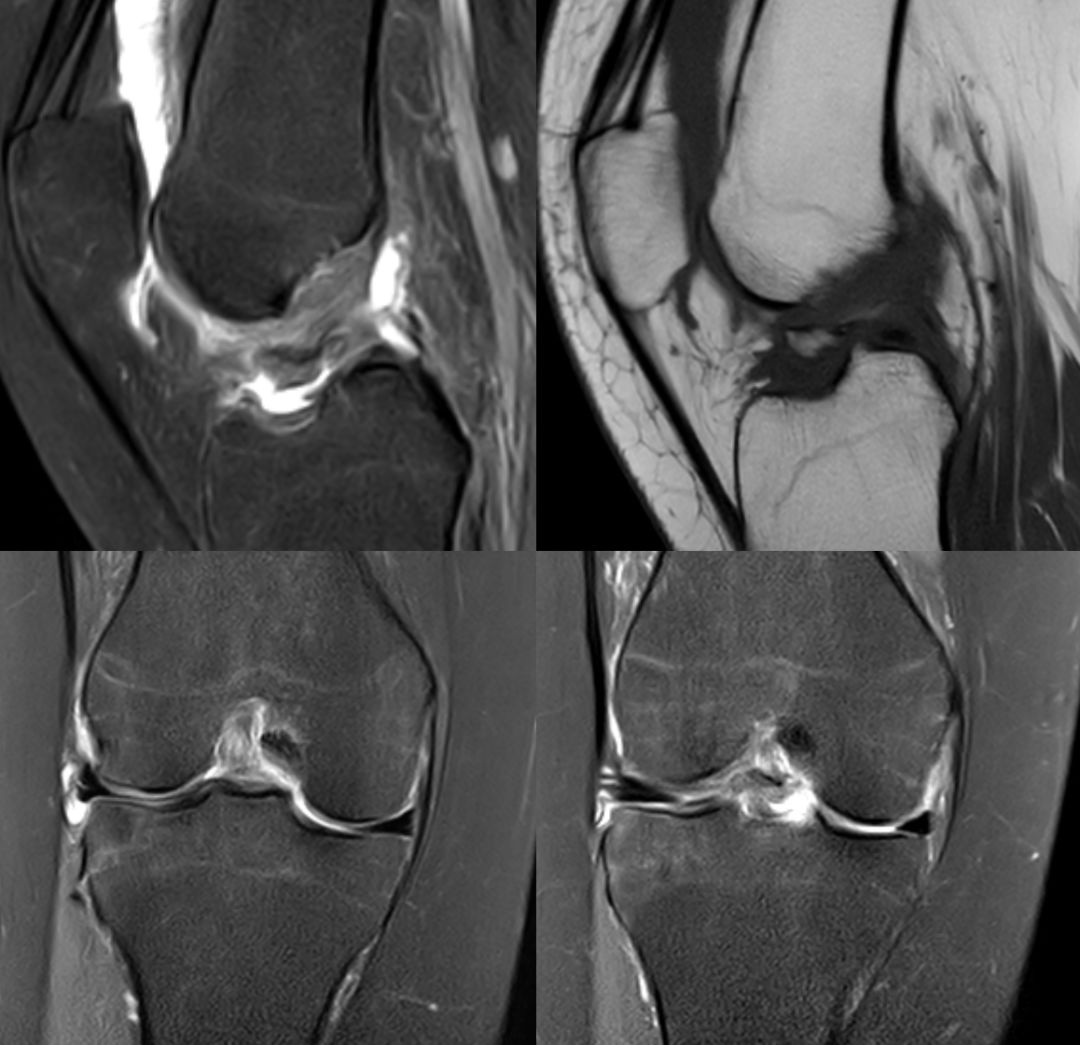

Segond骨折,因下肢过度内翻、内翻暴力所致胫骨平台外侧缘的撕脱性骨折。撕脱的骨折块较小,小骨片多位于腓骨头上方,且较少波及关节面而易被忽视。往往合并前交叉韧带损伤、半月板损伤及外侧副韧带损伤。

有文献报道,Segond 骨折合并有前交叉韧带(ACL)损伤的发生概率约为75%~100%,若没有得到及时处理,关节将会出现反复扭伤的现象,容易引发膝关节继发性损害,最终将导致关节过早的出现退变和骨关节病的发生。当怀疑Segond骨折,应该做MRI检查,评价膝关节组织损伤情况。

CASE 前交叉韧带下端撕脱骨折 韧带撕裂

下图前交叉韧带重建术后